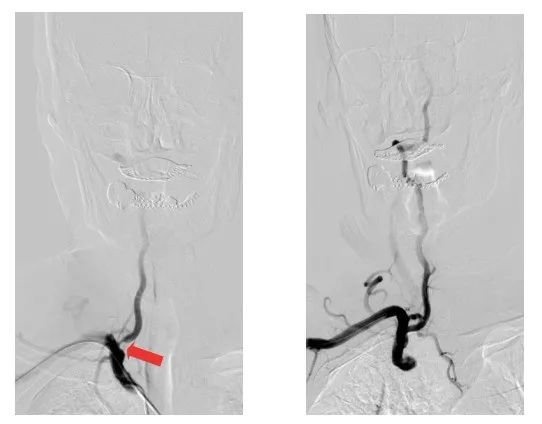

術(shù)前術(shù)后影像對比(紅色箭頭所指位置為狹窄處)

79歲的劉大爺,因反復(fù)頭昏頭暈不適來江陰市人民醫(yī)院就診。神經(jīng)內(nèi)科副主任醫(yī)師陸強彬為其行全腦動脈造影檢查后發(fā)現(xiàn),劉大爺?shù)挠覀?cè)頸內(nèi)動脈閉塞,右側(cè)椎動脈開口處重度狹窄,并向右側(cè)頸內(nèi)動脈代償供血。

醫(yī)療團隊僅用時40多分鐘,便通過右側(cè)橈動脈入路,成功在患者的椎動脈置入1枚支架。術(shù)后,患者的椎動脈狹窄解除,頭暈頭痛癥狀消失,即可下床活動,身體恢復(fù)良好。